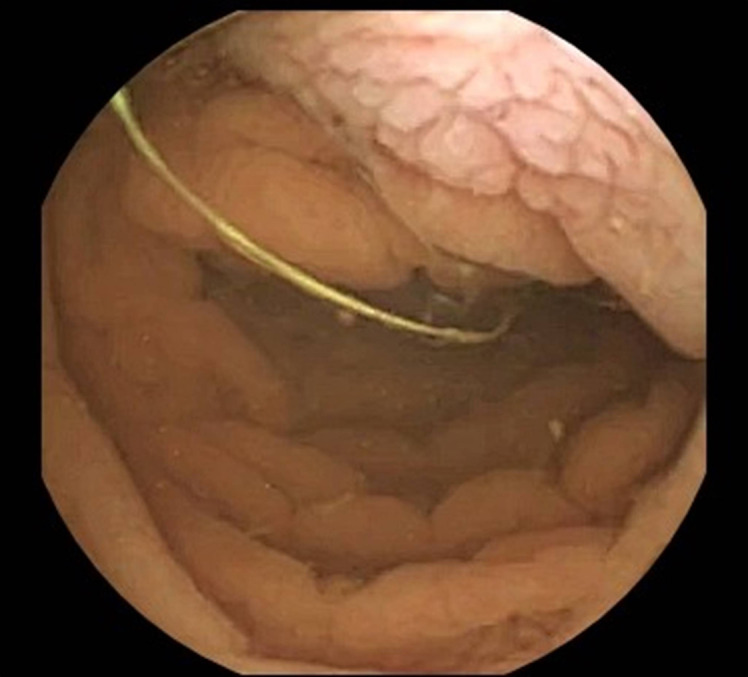

Common variable immunodeficiency enteropathy is a sprue-like disease, which may manifest as a severe malabsorption syndrome with nutritional deficits and cachexia. The authors report a case of a 33-year-old Afghan man, who presented to the emergency department due to chronic watery diarrhea and severe malnourishment. He had been previously misdiagnosed with celiac disease in his early adulthood; however, this was based on inconclusive findings. After a thorough diagnostic workup, the final diagnosis of common variable immunodeficiency enteropathy with symptomatic norovirus infection of the gut was obtained during his prolonged hospitalization. A slow but progressive improvement was observed with immunoglobulin replacement therapy, corticotherapy, and ribavirin treatment. This is a noteworthy case of a rare malabsorption disorder, and it reviews important aspects concerning the differential diagnosis of small bowel villous atrophy of unknown etiology, as well as gastrointestinal manifestations of common variable immunodeficiency disorder.